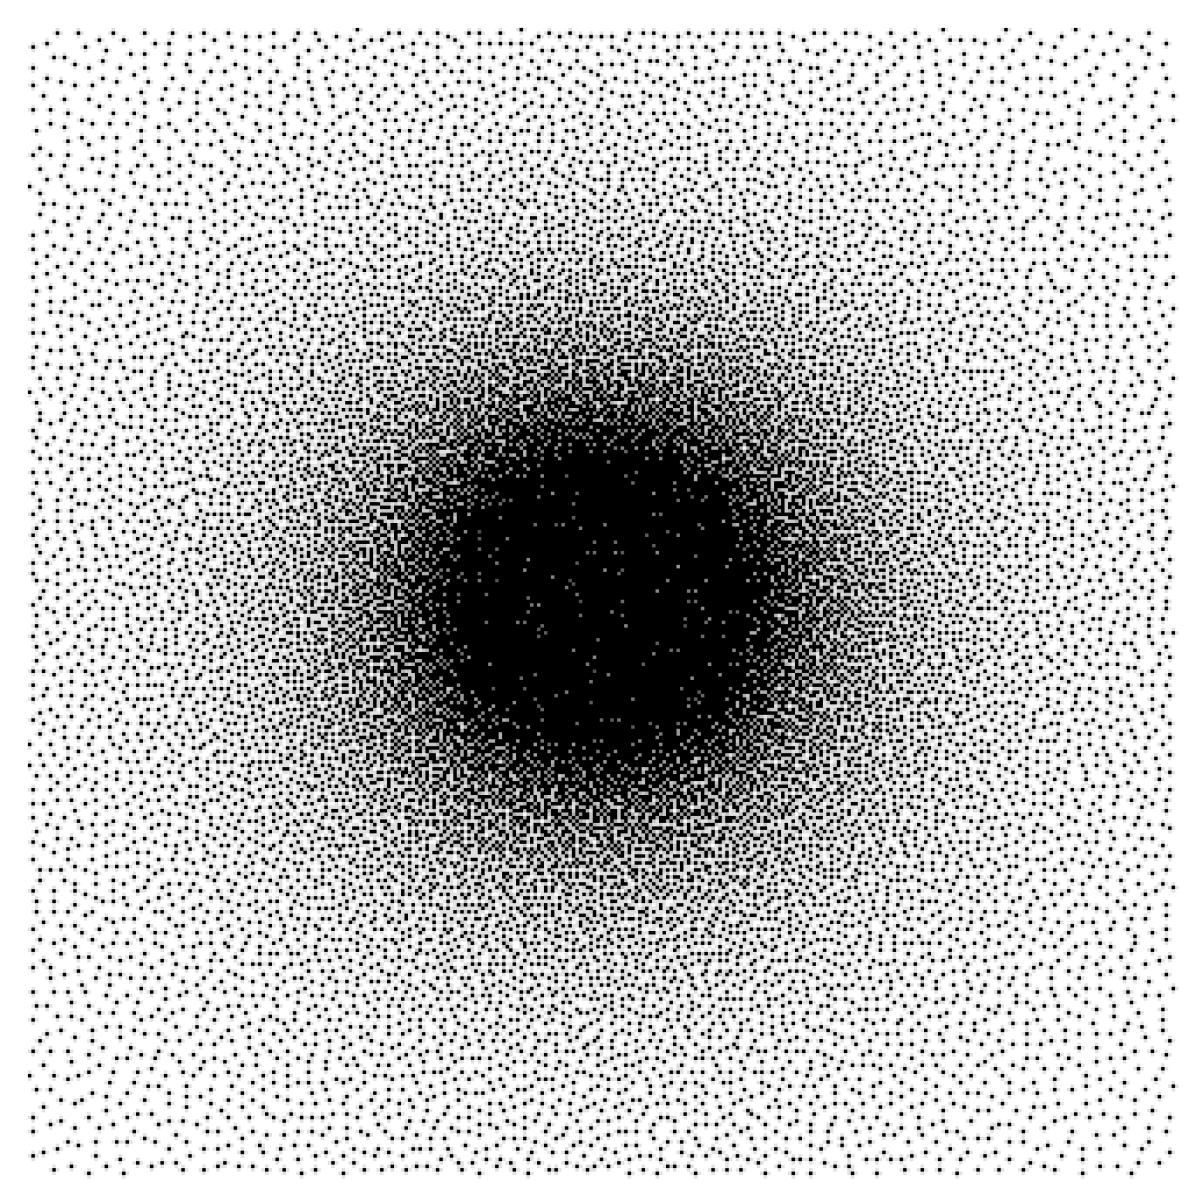

Training mismatch issue

While model-based reconstruction networks provide state-of-the art results in a large panel of applications, it is now well established that they suffer from a lack of adaptivity. This means that a network trained for a specific operator may have a significant performance drop if used for another operator . This drop can be evaluated as follows. Let denote two different operator parametrizations. Let and . Assume that and are the weights of a reconstruction network optimized for and respectively. We compare the quality of and in the third and fourth rows of Fig. 1. Observe the significant performance difference.

| Test case | MRI | CT | Deblurring |

To avoid this pitfall, we propose to train the network by minimizing (4) instead of (3). After providing some theoretical hints on why a favorable behavior may occur, we will carefully evaluate the performance of the resulting networks in Section 6 for MR image reconstruction from under-sampled data, CT imaging and image deblurring. We conclude that this learning approach yields a reconstruction network which is significantly more stable to variations of the forward operator. In addition, the performance of an unrolled network trained on a restricted family is only marginally worse than that of a network that would be trained and used for a single operator. It therefore provides a satisfactory answer to the adaptivity issue. We also address several questions raised by our methodology. Can the unrolled network trained on a family extrapolate to unseen operators? How to sample the space of admissible operators? What is the gain of this approach in comparison to more “universal approaches” such as plug-and-play (P&P) priors?

Model mismatch issue

Assume that we observe . Unfortunately, we only have access to an approximate knowledge of the true forward model . This can be due to an imprecise calibration of the sensing device or to the motion of a patient in a scanner for instance. We then face a blind inverse problem. A problem solved with such a model mismatch (i.e. with the operator in place of ), can lead to catastrophic reconstruction results, as illustrated in the last row of Fig. 1.

The drop of peak signal-to-noise ratio (PSNR) when using a network trained with the wrong operator can be as high as dB for the denoising net on the MRI experiment (see trained on , applied on ). This drop is more moderate, but yet really significant (MRI: dB, CT: dB, Blur: dB) for the unrolled net. This is a striking illustration of the strong dependency of a reconstruction network to the operator used at the training stage. We illustrate the artifacts that can appear when the operator is trained on a different operator for the MRI application in Fig. 4. We can clearly see horizontal stripes oscillating at a high frequency, suggesting that the network did not properly learn to reconstruct the corresponding Fourier coefficients.